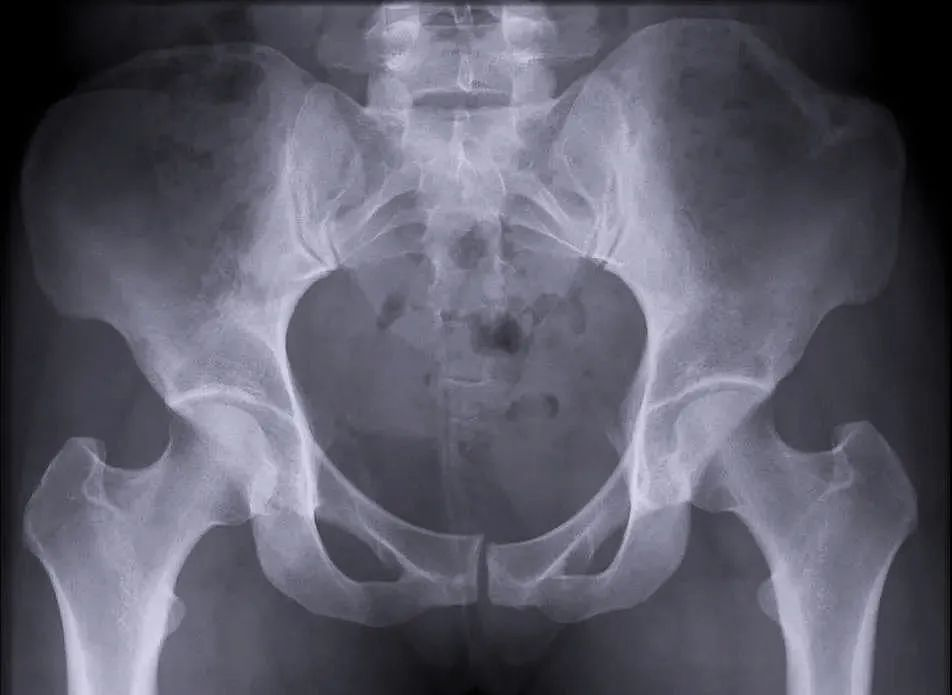

穩(wěn)定性骨折

另外,我們根據(jù)骨盆骨折是否穩(wěn)定可以分為穩(wěn)定性的骨折和不穩(wěn)定性的骨折。如果是不穩(wěn)定性的骨折醫(yī)生可能會建議病人進行手術治療,把不穩(wěn)定性的骨折變成穩(wěn)定性的骨折。